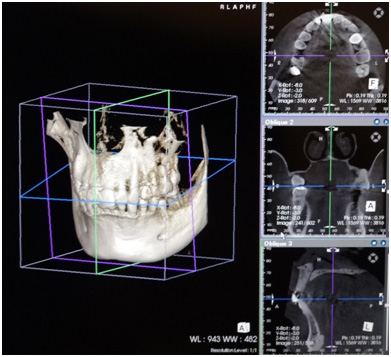

従来のレントゲン写真(平面)では診察することのできない血管や神経の位置を正確に把握するためには、3次元のレントゲン(3DCT)での撮影が必須となります。

当院では院内に3DCTを設置する事により、術後にもその場で問題が起きてないかの確認ができるため、より安全にインプラントの手術ができるようになっております。